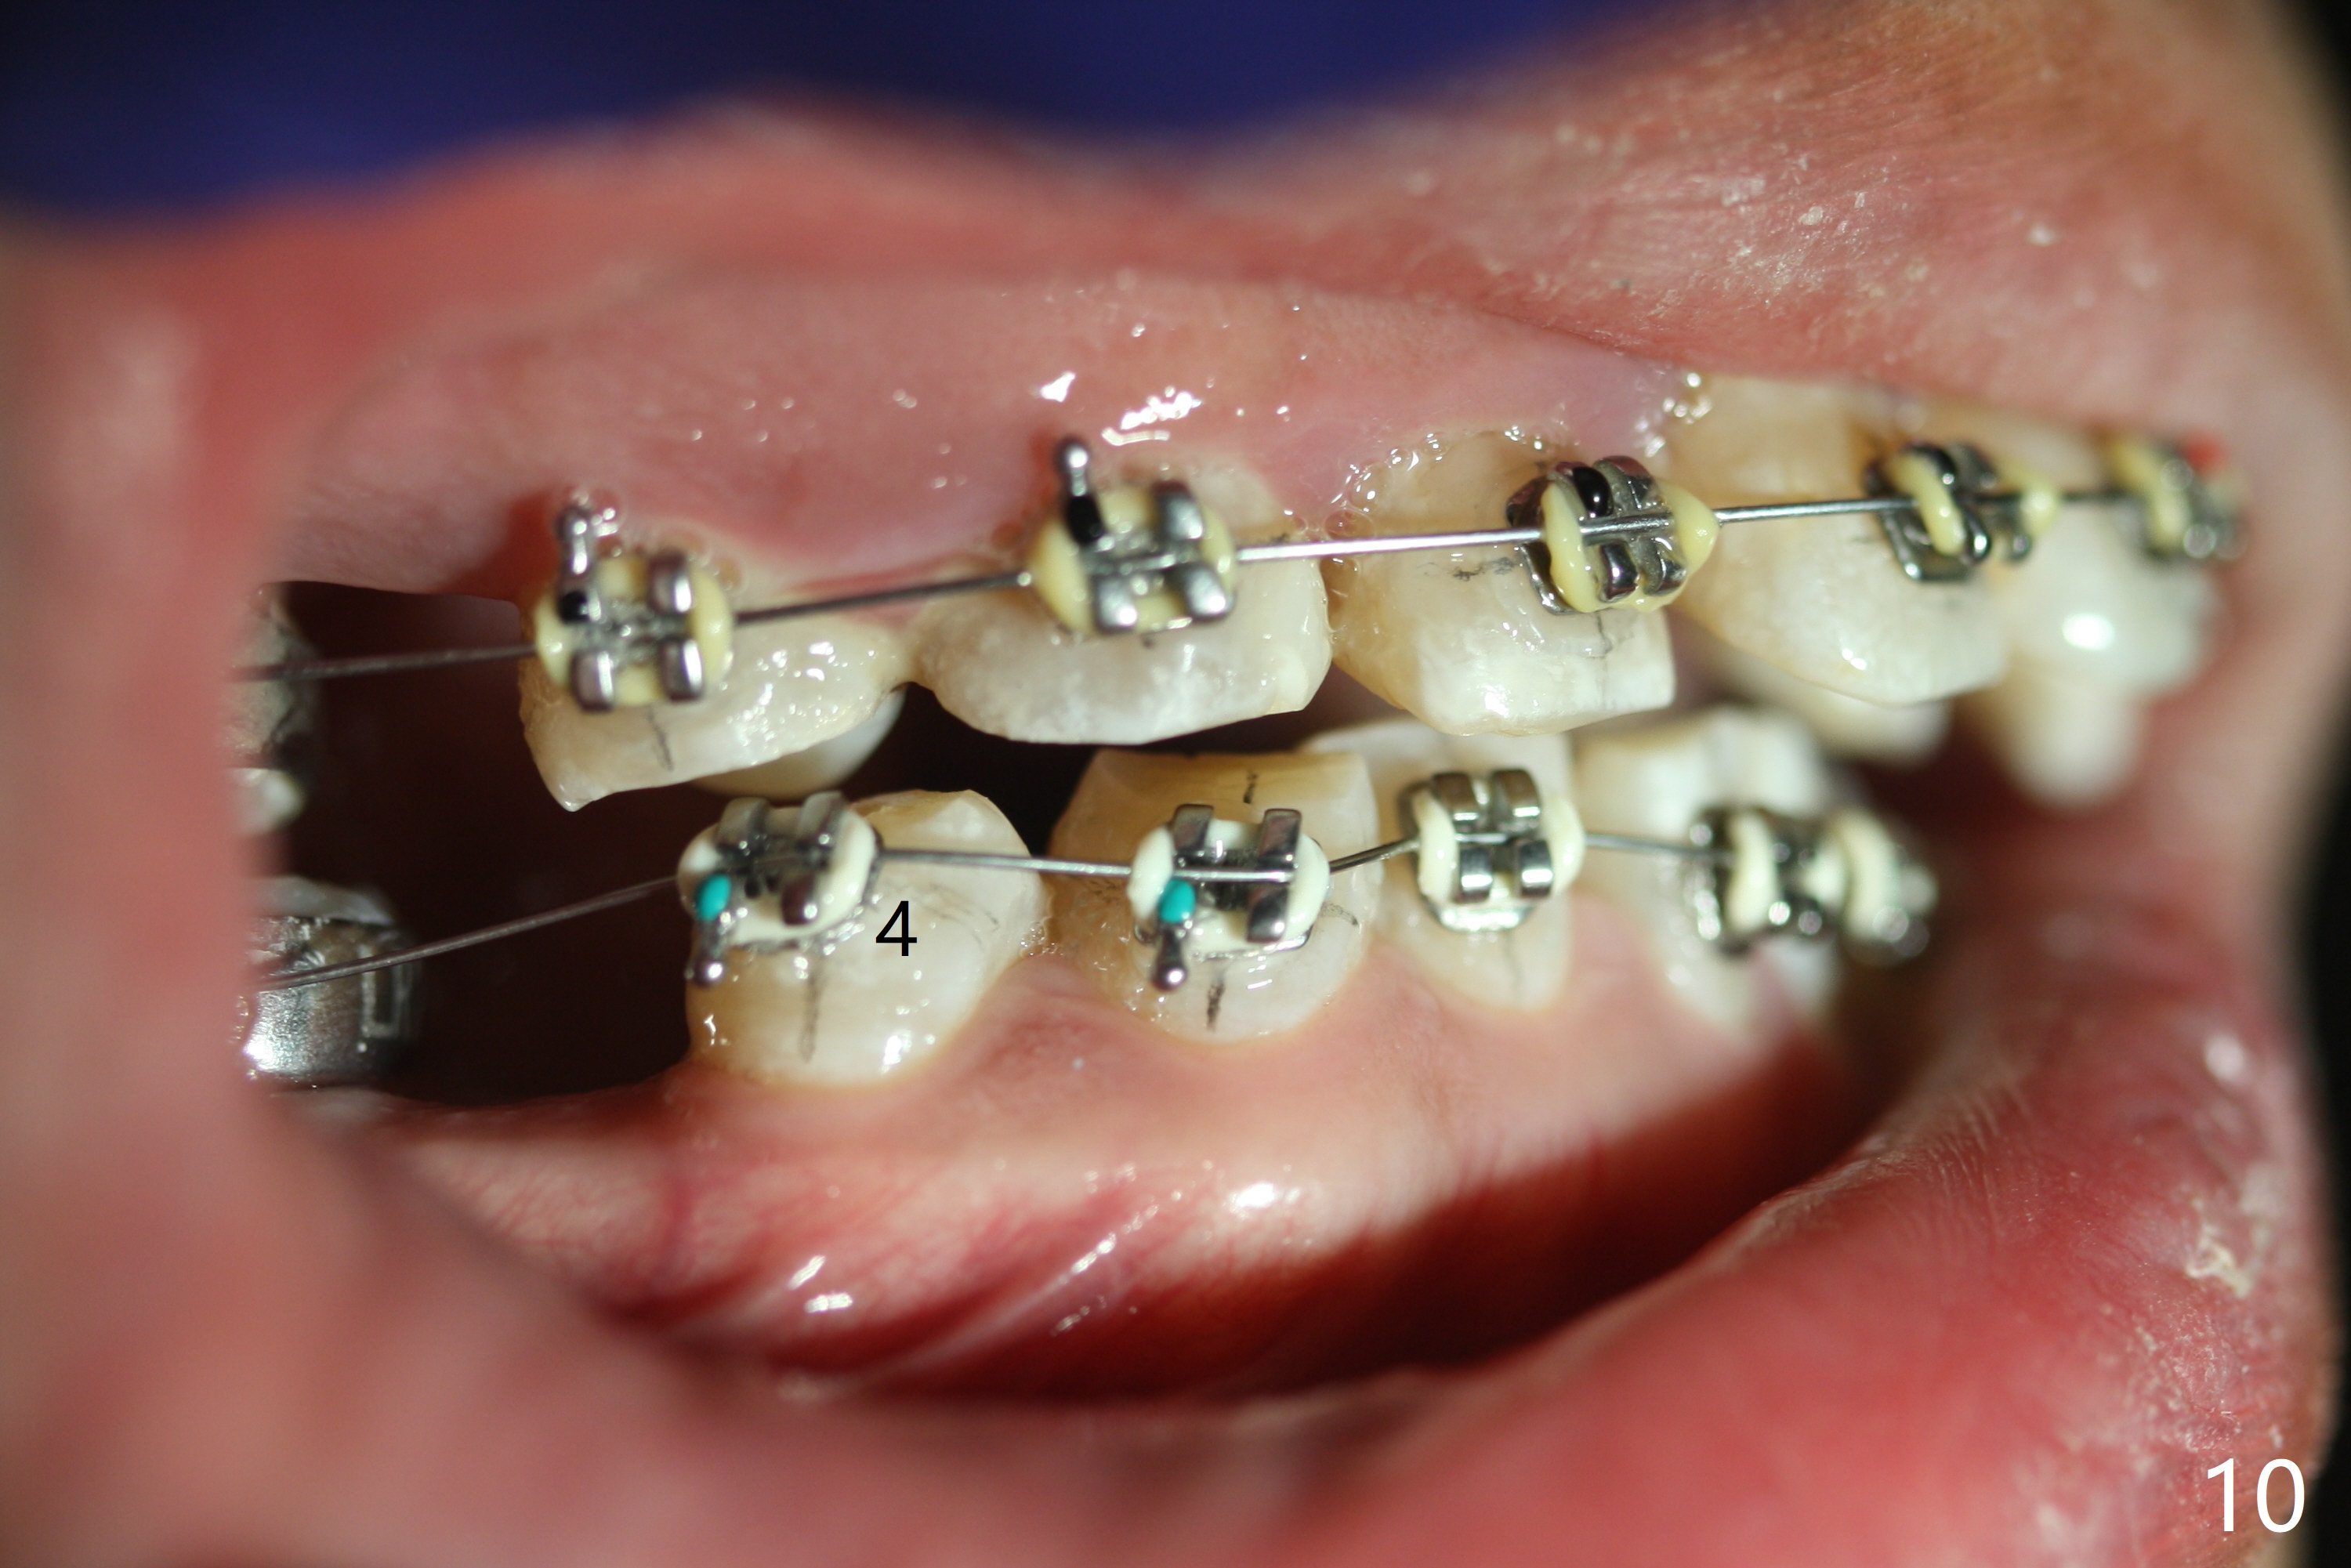

Severe crowding (Fig.1-7) appears to be alleviated especially 2 months after UR5 extraction. Diastemata seem to form mesial and distal to UR2 (Fig.8). Because of severe wear at UR3 (Fig.6), there is no bracket placement differential around it (Fig.8 (14 niti wire)). Lower bands and brackets are placed a week later (Fig.9-11). Because of tight space between LR4 and the opposing tooth (Fig.10), band adhesive is applied to L7 occlusal surface to open the bite (Fig.9). There is an abrupt kink of 12 niti wire between LL4 and 6 (Fig.11). The latter does not improve much in a month; the wires remain the same (Fig.12). For LL2, LR4 has been retracted for ~ 1 month (Fig.13). There is mild tension when 18 ss wire is inserted between LL4 and 6 five point five months post banding (Fig.14). UR4 has been distalized for a month using buccal power chains x3 resulting in rotation; to counter the rotation, a lingual button is placed with power chain x3 lingual and x2 buccal (Fig.15). With space gaining, it is time to finish definitive filling (Fig.16 *). Next visit check midlines, overjet, interdigitation, and molar classification. R4s distalize, but associate with rotation because of power chains buccal and lingual 8 months post banding (Fig.17,18). With the use of the same wires, power chains are applied lingual to continue distalization and rotation correction (Fig.20,21). Lingual buttons are placed at L2s buccalization (Fig.19) and mesialization (Fig.22,23). It appears that space should be created distal to LR3. That is that the lower anterior teeth should be shifted to the right, although it may be not appropriate for the midline.